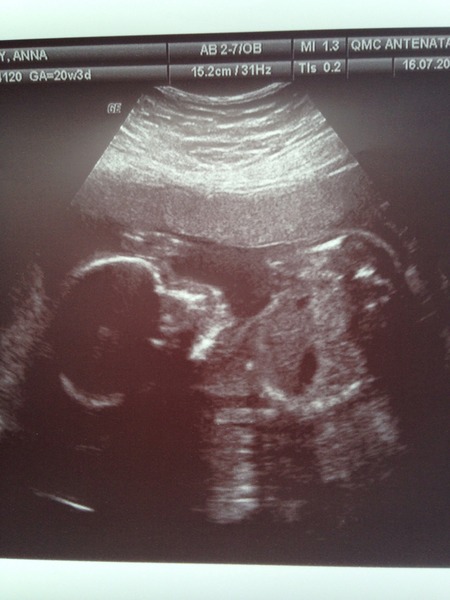

Thanks all! I think I am the first pink! Here's her picture-not a great one, she wasn't being very cooperative!